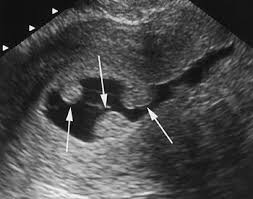

Principalele instrumente de diagnostic pentru evaluarea polipilor endometriali includ ecografia transvaginală, ecografia cu infuzie salină și histeroscopia, aceasta din urmă fiind cea care stabileste cu certitudine diagnosticul. Examinarea ecografică transvaginală poate orienta diagnosticul diferențial cu un nodul fibromatos intracavitar prin utilizarea examinării Doppler, unde în cazul polipilor se poate identifica un singur vas arterial de hrănire.

Polip intrauterin